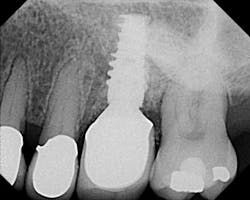

X-ray six months after postop. Regeneration using laser, Emdogain, and DFDBA (Demineralized Freeze-Dried Bone Allograft).Erbium lasers are powerful tools that give the clinician the ability to achieve predictable periodontal regeneration, enhance the surgical experience for the clinician, and create a more pleasant healing experience for the patient.It is important to understand that a laser does not replace sound biology, science, and diagnostics. Lasers are not magical. It is foolish to think that you can take a laser light, direct it into a patient’s periodontal pocket, and expect a supernatural result. As with anything else, one must attain extensive training in the use of lasers, and use sound clinical judgment prior to applying laser technology into patient care. Author bioMark Schlesinger, DDS, is a diplomate of the American Board of Periodontology and a clinical assistant professor in the Department of Periodontics and Implant Dentistry at the New York University College of Dentistry. You may contact him at The Diamond Schlesinger Group, nyimplantdentistry.com or nylaserinstitute.com.